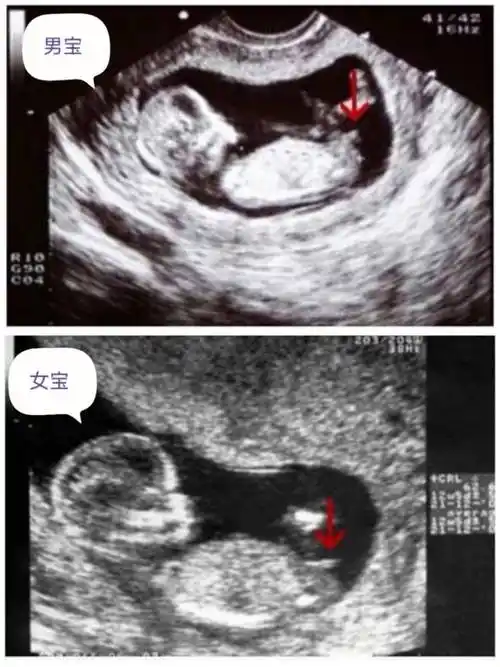

这些nt看男女诀窍建议收藏